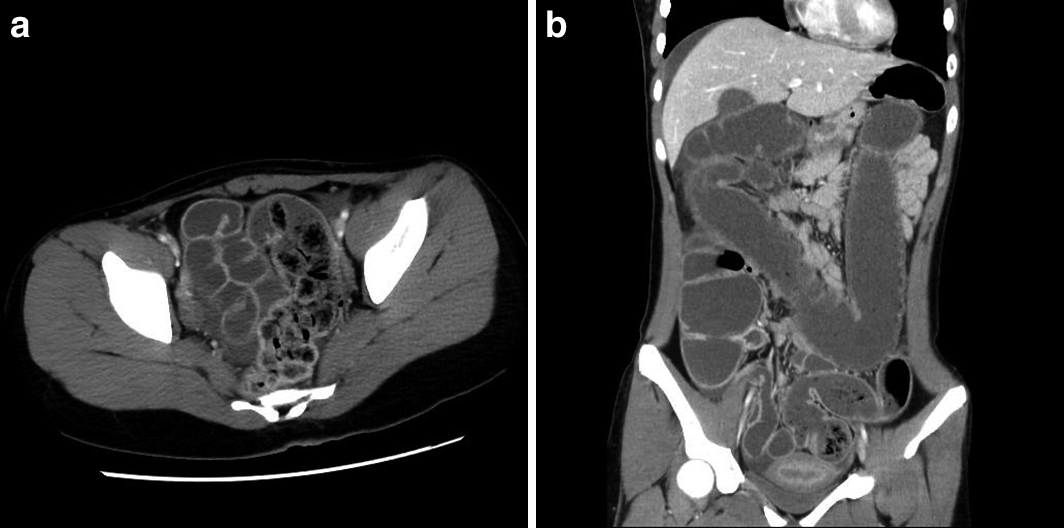

腹部CT所見:直腸からS状結腸に便塊の貯留を認め,口側の結腸,小腸に著明な拡張,液貯留がみられた.拡張した腸管には造影効果を認めた.横行結腸に浮腫性壁肥厚を認めた.中等量の腹水を認めた(Fig. 2).

a. Abdominal CT showed coprostasis in the rectum and the sigmoid colon. b. The small and large intestine were markedly extended and filled with content fluid. The extended intestine showed contrast enhancement. Edematous wall thickening of the transverse colon were seen. Ascites was found.